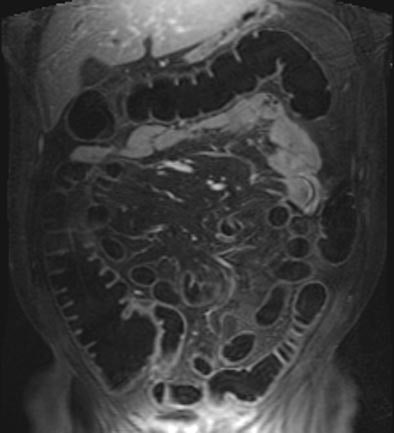

| T1-weighted GRE MR colonography images of the same patient. Top: water-filled colon following rectal enema. Bottom: study obtained on another day, following rectal insufflation with room air. Images courtesy of Dr. Thomas Lauenstein. |

Another new study by the Essen radiologists sought to determine if either air or water as a colon insufflation agent performed better in dark-lumen MRC (Journal of Magnetic Resonance Imaging, February 2004, Vol. 19:2, pp. 216-221).

The group performed dark-lumen MRC followed by conventional colonoscopy on 50 patients suspected of having colorectal pathologies, who were randomized into two groups of 25 patients undergoing either tap water or room-air insufflation prior to imaging. In addition, five healthy volunteers agreed to undergo MRC twice, once with water and once with room air, prior to the conventional exam.

MR data were acquired using a combination of two surface coils on a 1.5-tesla Magnetom Sonata scanner (Siemens Medical Solutions, Erlangen, Germany). T1-weighted 3-D gradient-echo images (96 slices, effective slice thickness 1.54 mm) were acquired in the coronal plane, and sequence parameters included TR/TE 3.1/1.1 msec, flip angle 12º, FOV 450 x 450. Then a paramagnetic contrast agent, Gd-BOPTA, was administered intravenously (0.2 mmol/kg) and the same imaging sequence was repeated after a 75-second delay.

The image-quality rating trended better with air distension (1.2 for air versus 1.3 in water among the volunteers), but the difference wasn't statistically significant. However, the use of air produced significantly better colonic distension than water (p<0.05), with a mean rating of 1.07 for air compared to 1.31 for water among the patients.

In patients or volunteers, artifacts were not a problem with either air or water distension, although there were a few artifacts related to motion or wrapping. However, there were statistically significant differences in the contrast-to-noise ratio, with a mean of 43.5 for air distension and a mean of 36.3 (p< 0.05) for water overall. Preferences among the five volunteers were inconclusive: two preferred each method, and one preferred neither.

Moreover, eight of nine lesions were detected on water-filled MRC, and no lesions were missed when air distension was used. And, they said, the use of ultrashort (0.6-second) echo times virtually eliminated the presence of susceptibility artifacts in the presence of air distension because "there is simply not time for disphasing to occur. Thus it was not surprising that image quality of air- and water-distended datasets did not reveal a statistically significant difference."

"We conclude that MRC...can be performed using either air or water as a distending agent," they wrote. Still, "slightly better CNR and improved distension of the rectum and sigmoid colon seem to favor air distension."